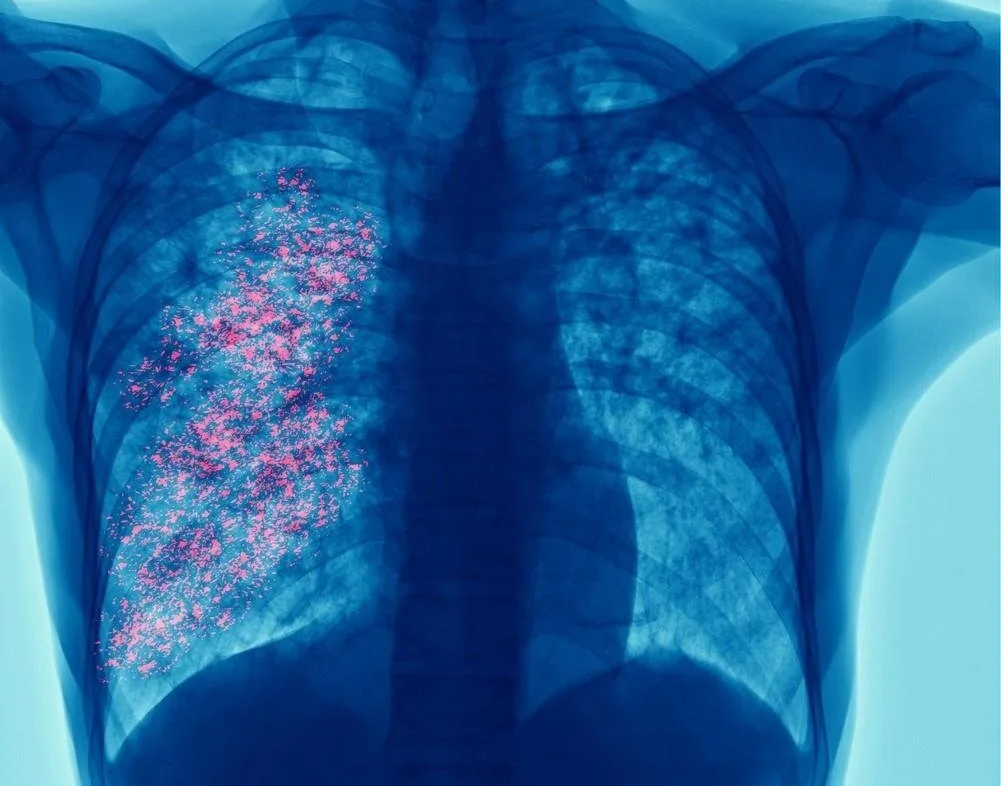

【於慶中/綜合報導】每年3月24日是「世界結核病日(World TB Day)」,全球各界藉此機會呼籲重視肺結核防治。今年(2026年)在結核病死灰復燃且抗藥性日益嚴重的情況下,澳洲雪梨大學等國際研究團隊公布新發現,為對抗這種全球頭號感染殺手帶來新希望。

世界衛生組織(WHO)指出,結核病(TB)在已開發國家曾經大幅減少後,如今再度回升,且越來越多菌株對現有最佳抗生素產生抗藥性,每年奪走超過百萬條人命。結核病由結核分枝桿菌(Mycobacterium tuberculosis)引起,可透過咳嗽或呼吸產生的飛沫傳播,雖然可治癒,但完整療程長達數月,導致患者容易中斷治療,進而加速抗藥性菌株出現。

全球約有四分之一人口曾感染結核菌,多數處於潛伏狀態,免疫力較弱或社經條件較差者,發病風險更高。